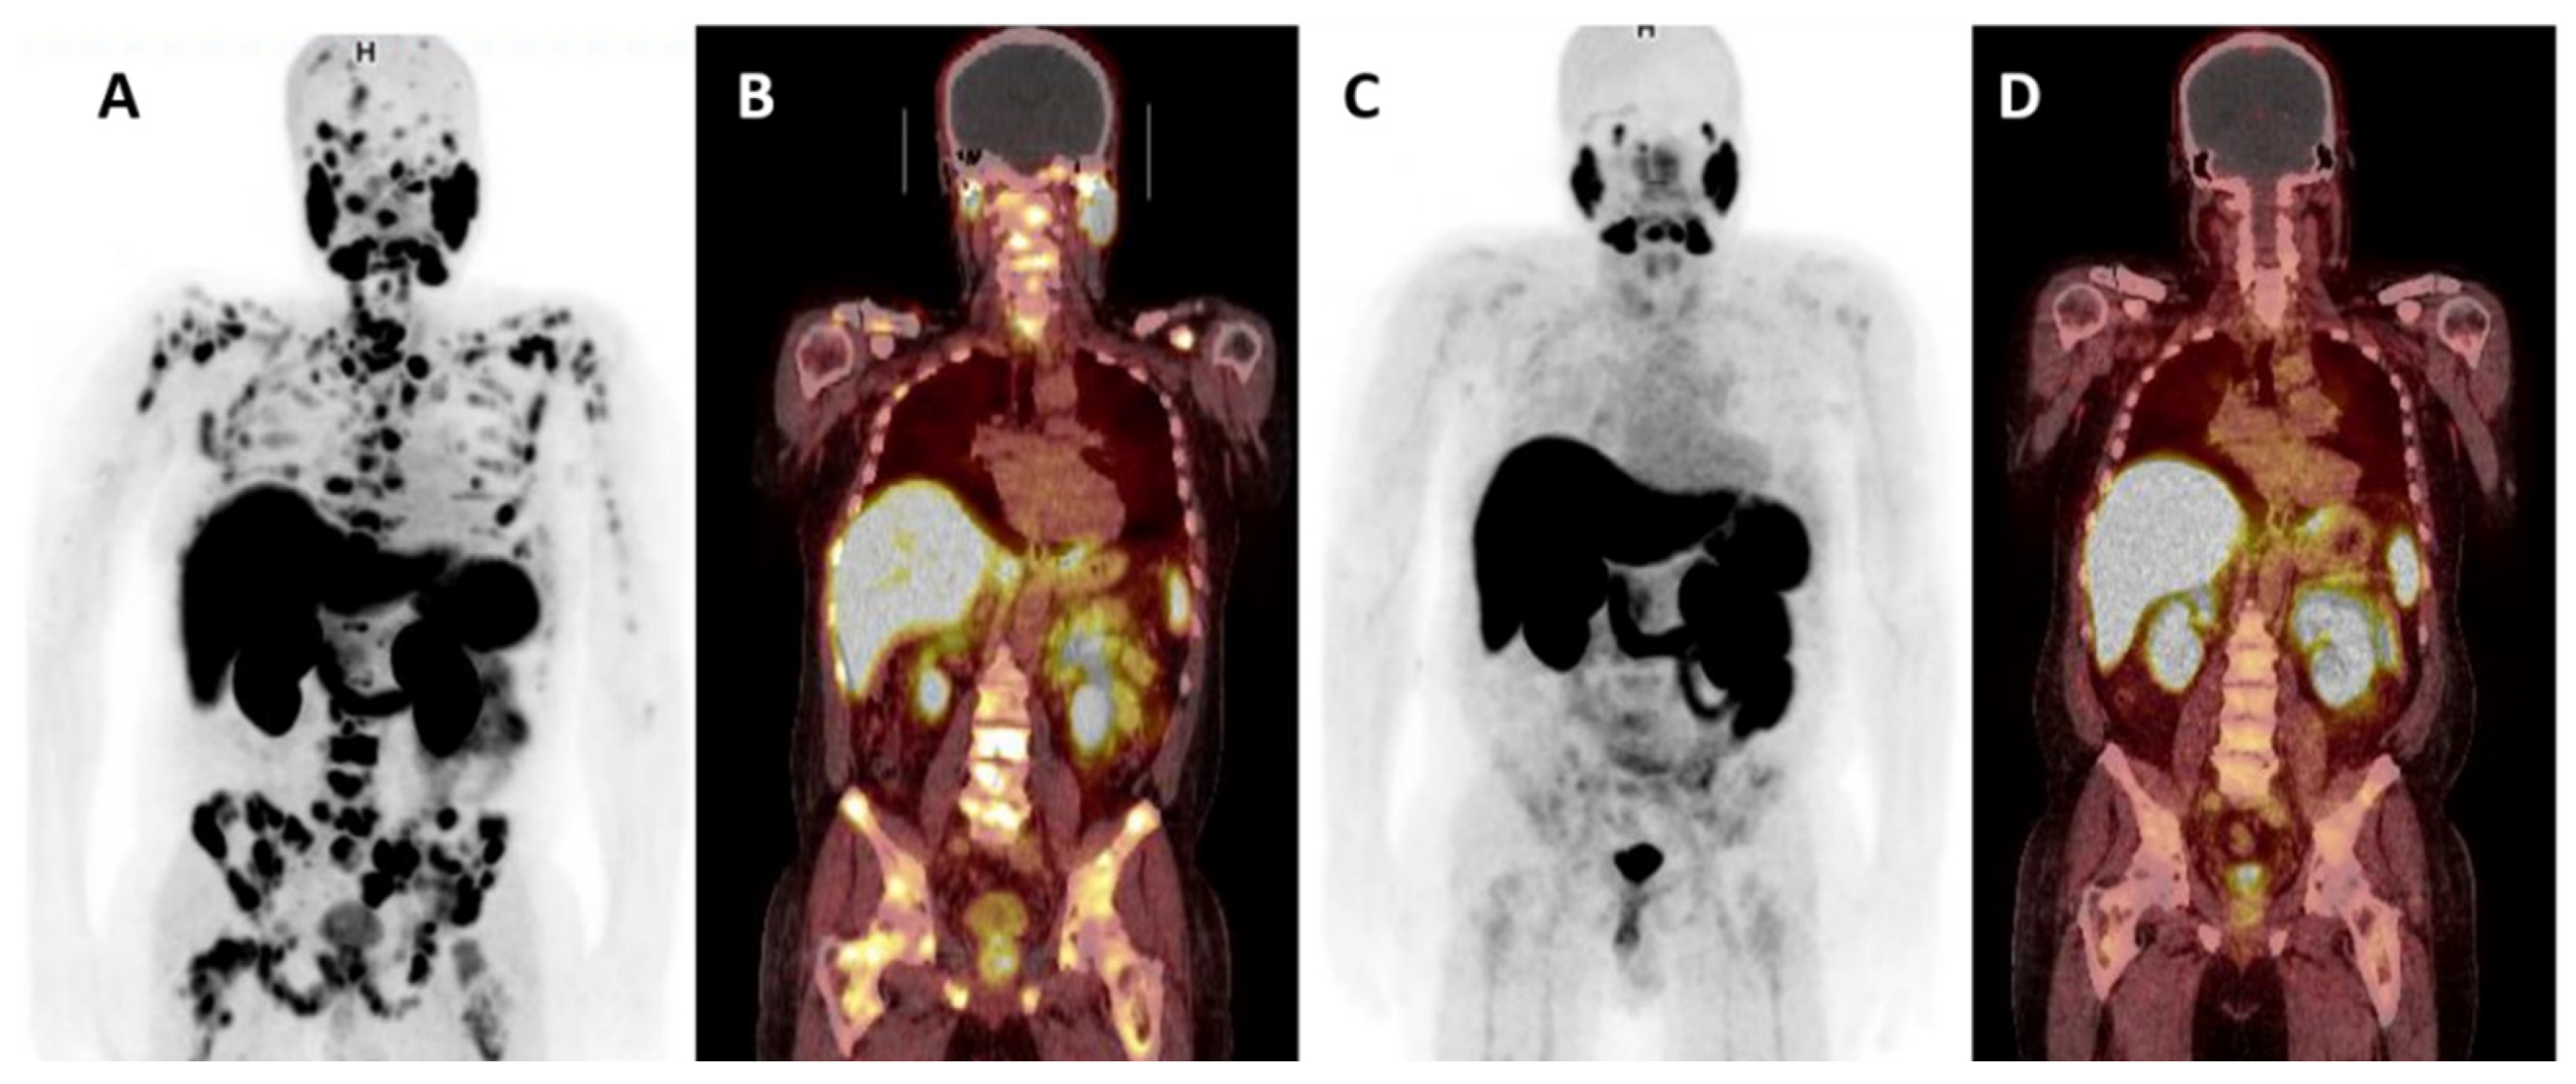

- Perez, P.M.; Hope, T.A.; Behr, S.C.; van Zante, A.; Small, E.J.; Flavell, R.R. Intertumoral Heterogeneity of 18F-FDG and 68Ga-PSMA Uptake in Prostate Cancer Pulmonary Metastases. Clin. Nucl. Med. 2019, 44, e28–e32. [Google Scholar] [CrossRef]